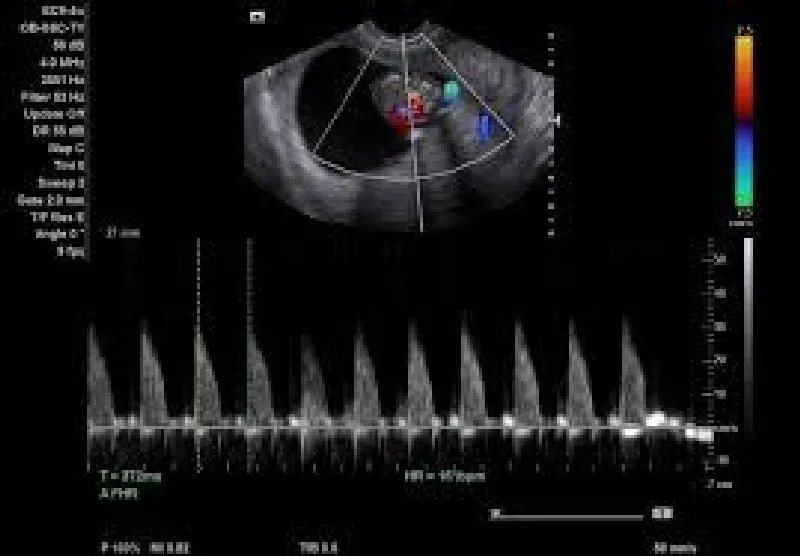

No Brasil, aproximadamente 50 mil médicos exercem a Ultrassonografia, com mais de 10 variações do exame, que pode ser recomendado a gestantes, pessoas com problemas digestivos ou até para verificar veias e artérias. Por isso, existe a preocupação de atender a essa especialidade médica com a mais adequada impressora para aparelho de ultrassom.